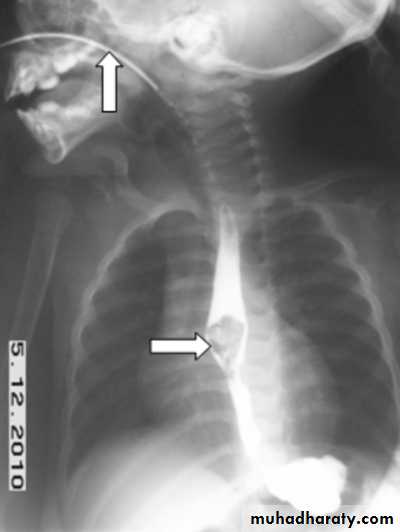

CausesEsophageal atresia

Types:• isolated atresia 8%

• Proximal fistula with distal atresia 1%

• Proximal atresia with distal fistula 85%

• Double fistula with intervening atresia 1%

• Isolated fistula [H-type] 4%